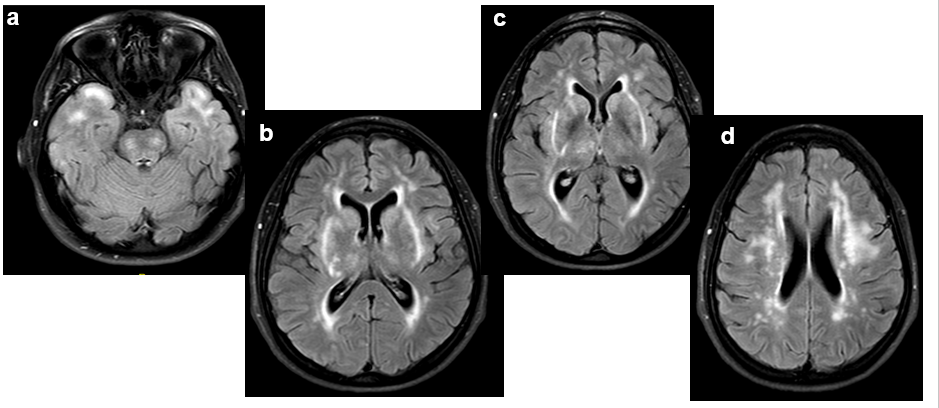

Tras los hallazgos y la sospecha clínica, se decide realizar estudio con RM a la hermana del paciente, de 47 años y sin antecedentes patológico (RM cerebral 2).

RM cerebral 2 (FLAIR-axial): Leucopatía extensa, confluente y en localizaciones características: en polos temporales anteriores (2a), en cápsulas externas (2b-c), y sustancia blanca subcortical con cierto respeto de lóbulos occipitales (2d).